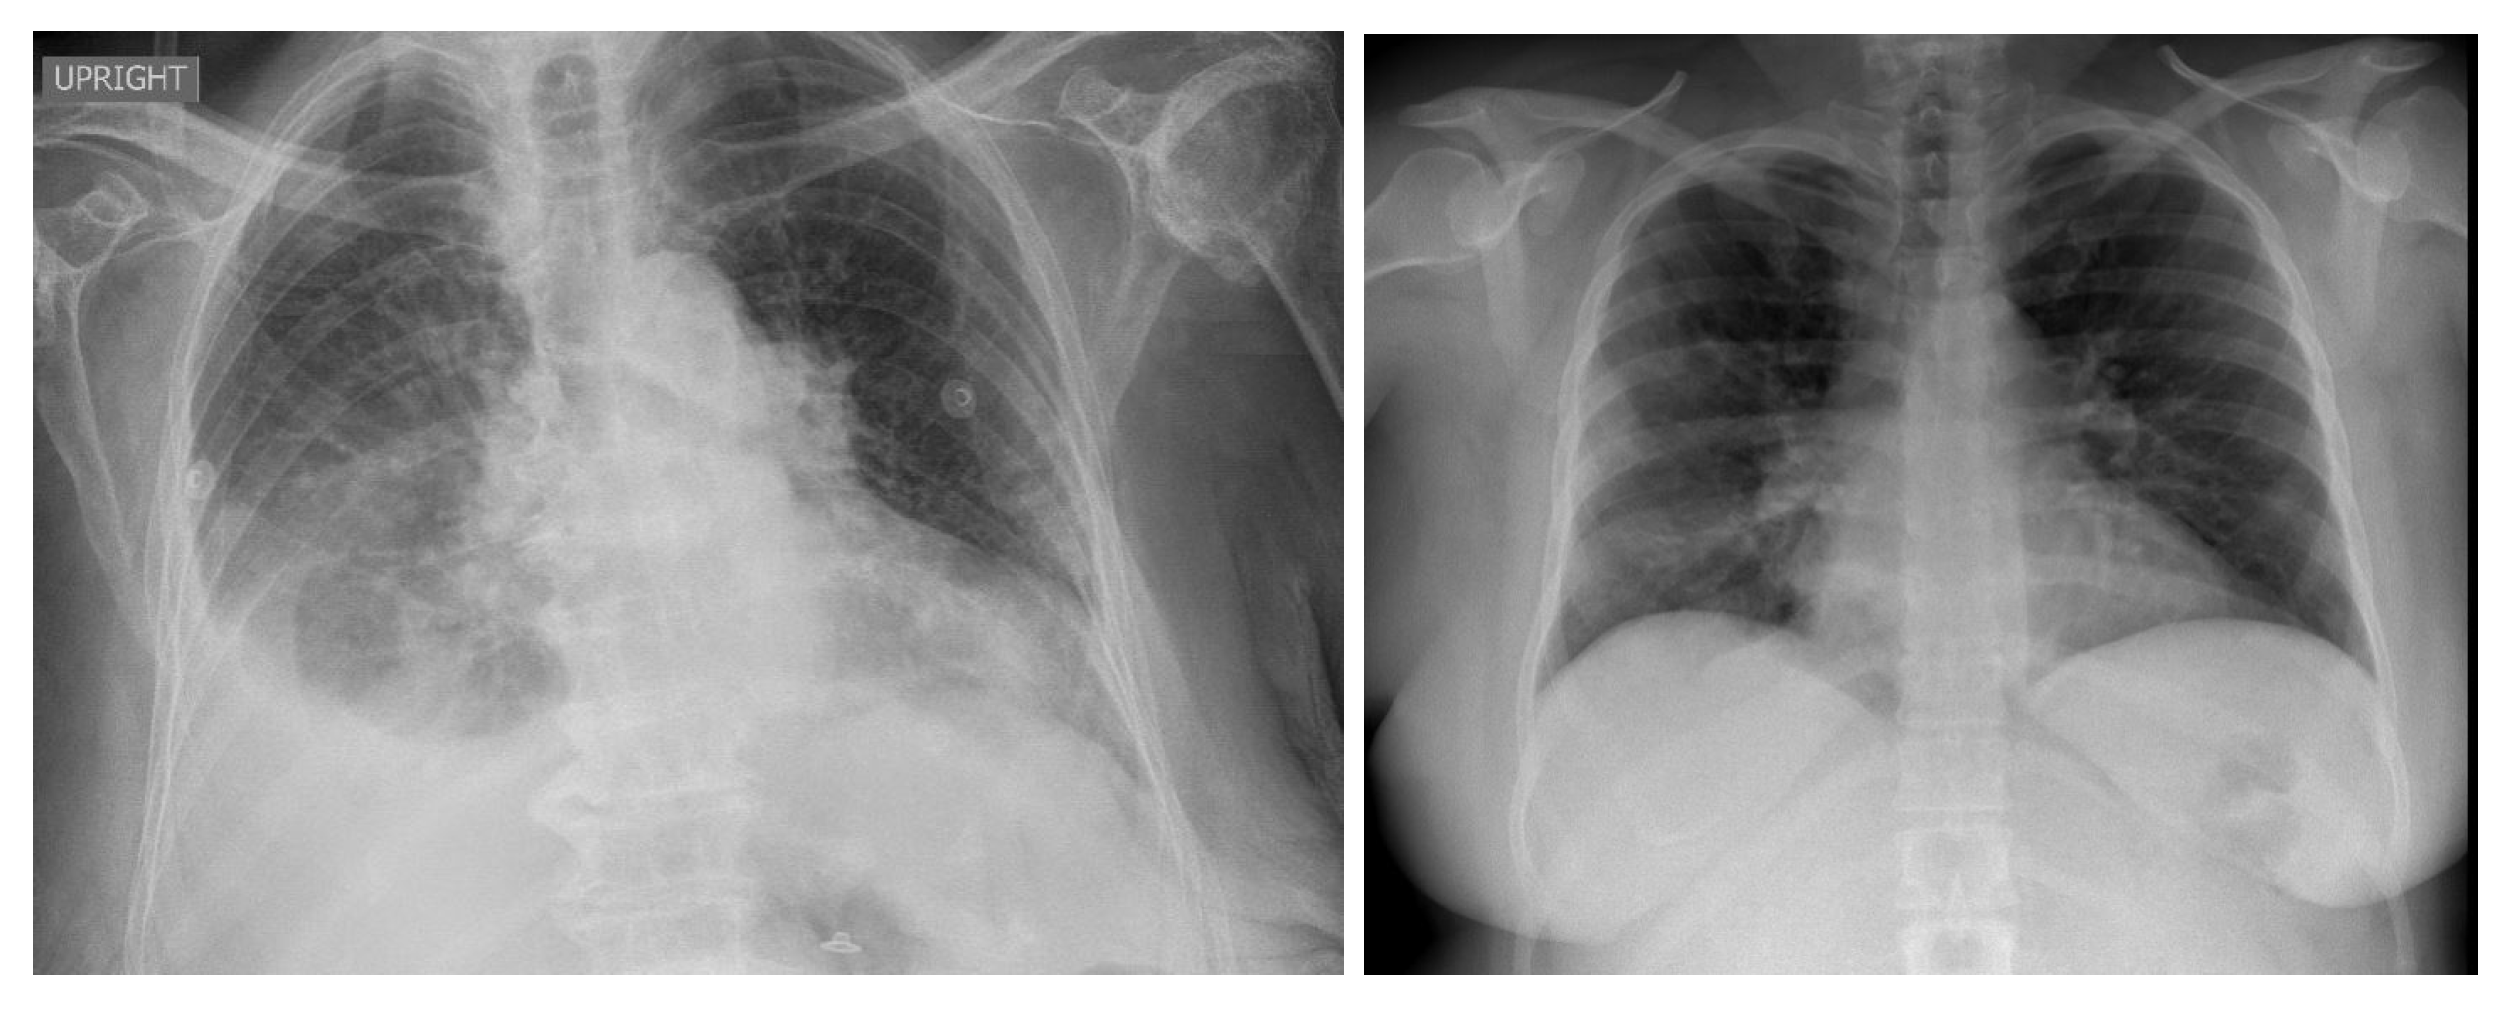

3.4.1. NIH Dataset

3.4.2. COVID-19 Image Data Collection

3.4.3. COVID-19 Radiography

3.4.4. BIMCV COVID19+

3.4.5. Montfort Dataset